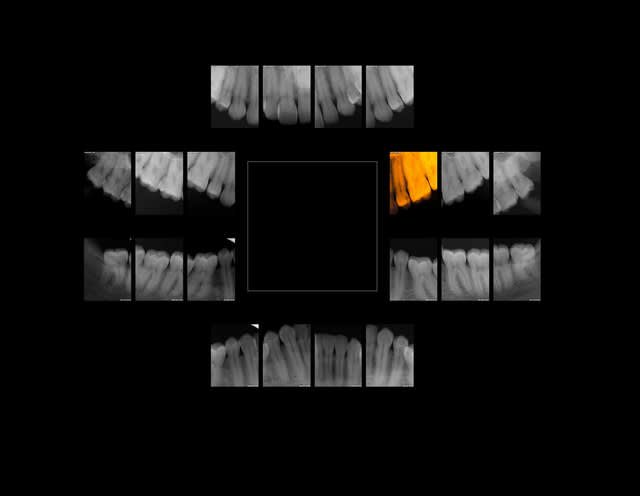

12/03/2014 à 16h34

Fidélisation ou risquer de passer pour un méchant dentiste avide.

Patient qui vient car son plombage sur 28 est tombé.

Faut il repondre à la demande de la patiente en faisant un sc17 en optimisant la nomenclature voir un sc33 puis une couronne alors qu'il y a une jolie féllure qui explique la fuite de la restauration précédente.

ou passer pour un voleur en proposant un implant pour remplacer 26 et faire l'extraction de 28 qui ne demande que cela.

réponse plus tard en voyant si la patiente revient.

R1c zzorbg - Eugenol